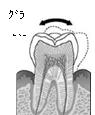

実はご自身の歯は簡単に動くのです。

ご自身の歯は歯根膜というクッションによって覆われていますから

物と物を噛んだ時に一瞬当たった後、動いているのです。

ご自身の歯は動くもの、

インプラントは動かないもの、

なのです。